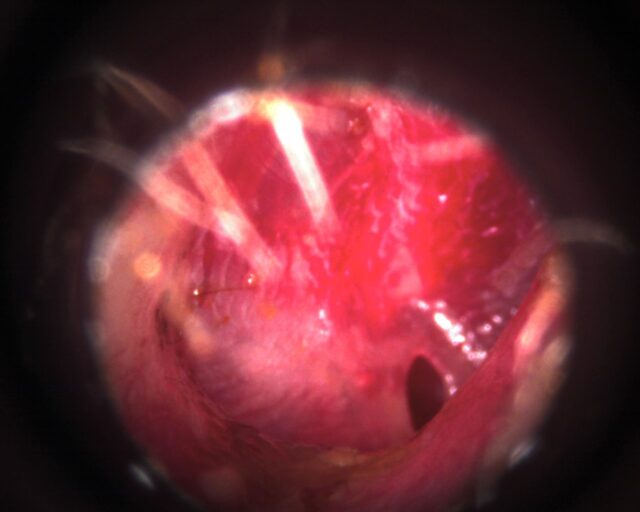

Ruptured ear drum by syringing!

A client came in with this ear drum. He felt water in his mouth straight after the syringe.